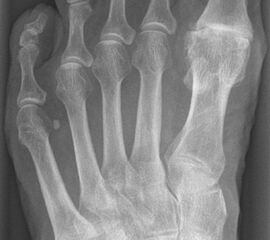

• Röntgenaufnahmen des Vorfußes (unter Belastung) im dorsoplantaren und seitlichen Strahlengang (Abb. 1a+b)

• Beurteilung des Erkankungsstadiums anhand der typischen Arthrosekriterien (Einteilung nach Regnauld). Beurteilung des Intermetatarsal-Winkels (IMA), des Hallux valgus-Winkels (HVA), da nur geringe Korrekturmöglichkeit durch die Osteotomieebene, darüber hinaus evtl. zusätzliche basisnahe MT-I-Korrektur notwendig